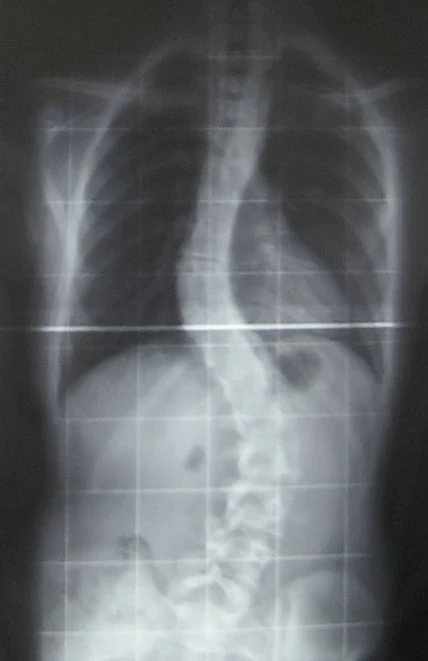

В ранних стадиях искривления выявляются лучше всего тестом «в наклоне». При этом пациент наклоняется вперёд со свободно опущенными руками. Проверяющий смотрит сзади на позвоночник и отмечает асимметрию — выступающее ребро, возвышающиеся с одной стороны ребра или лопатку, искривления позвоночника. Величина искривления позвоночника измеряется с помощью рентгеновского снимка всего позвоночника стоя. Возможны и врождённые рёберные деформации и деформации тел позвонков. С помощью этой информации можно отличить идиопатический и врождённый сколиоз. На рентгеновском снимке в боковой проекции можно также определить, есть ли врождённые деформации в этой плоскости или нарушения нормальных изгибов позвоночника — физиологических кифозов и лордозов.

Схема анализа рентгеновского снимка для определения угла искривления разработана американским ортопедом Дж. Коббом (англ. John Robert Cobb). Угол искривления, измеренный по рентгеновским снимкам называется «углом по Коббу». Для определения угла деформации на передне-задней рентгенограмме проводят две линии, параллельных замыкательным пластинкам нейтральных позвонков. В точке пересечения этих линий измеряют угол сколиоза.